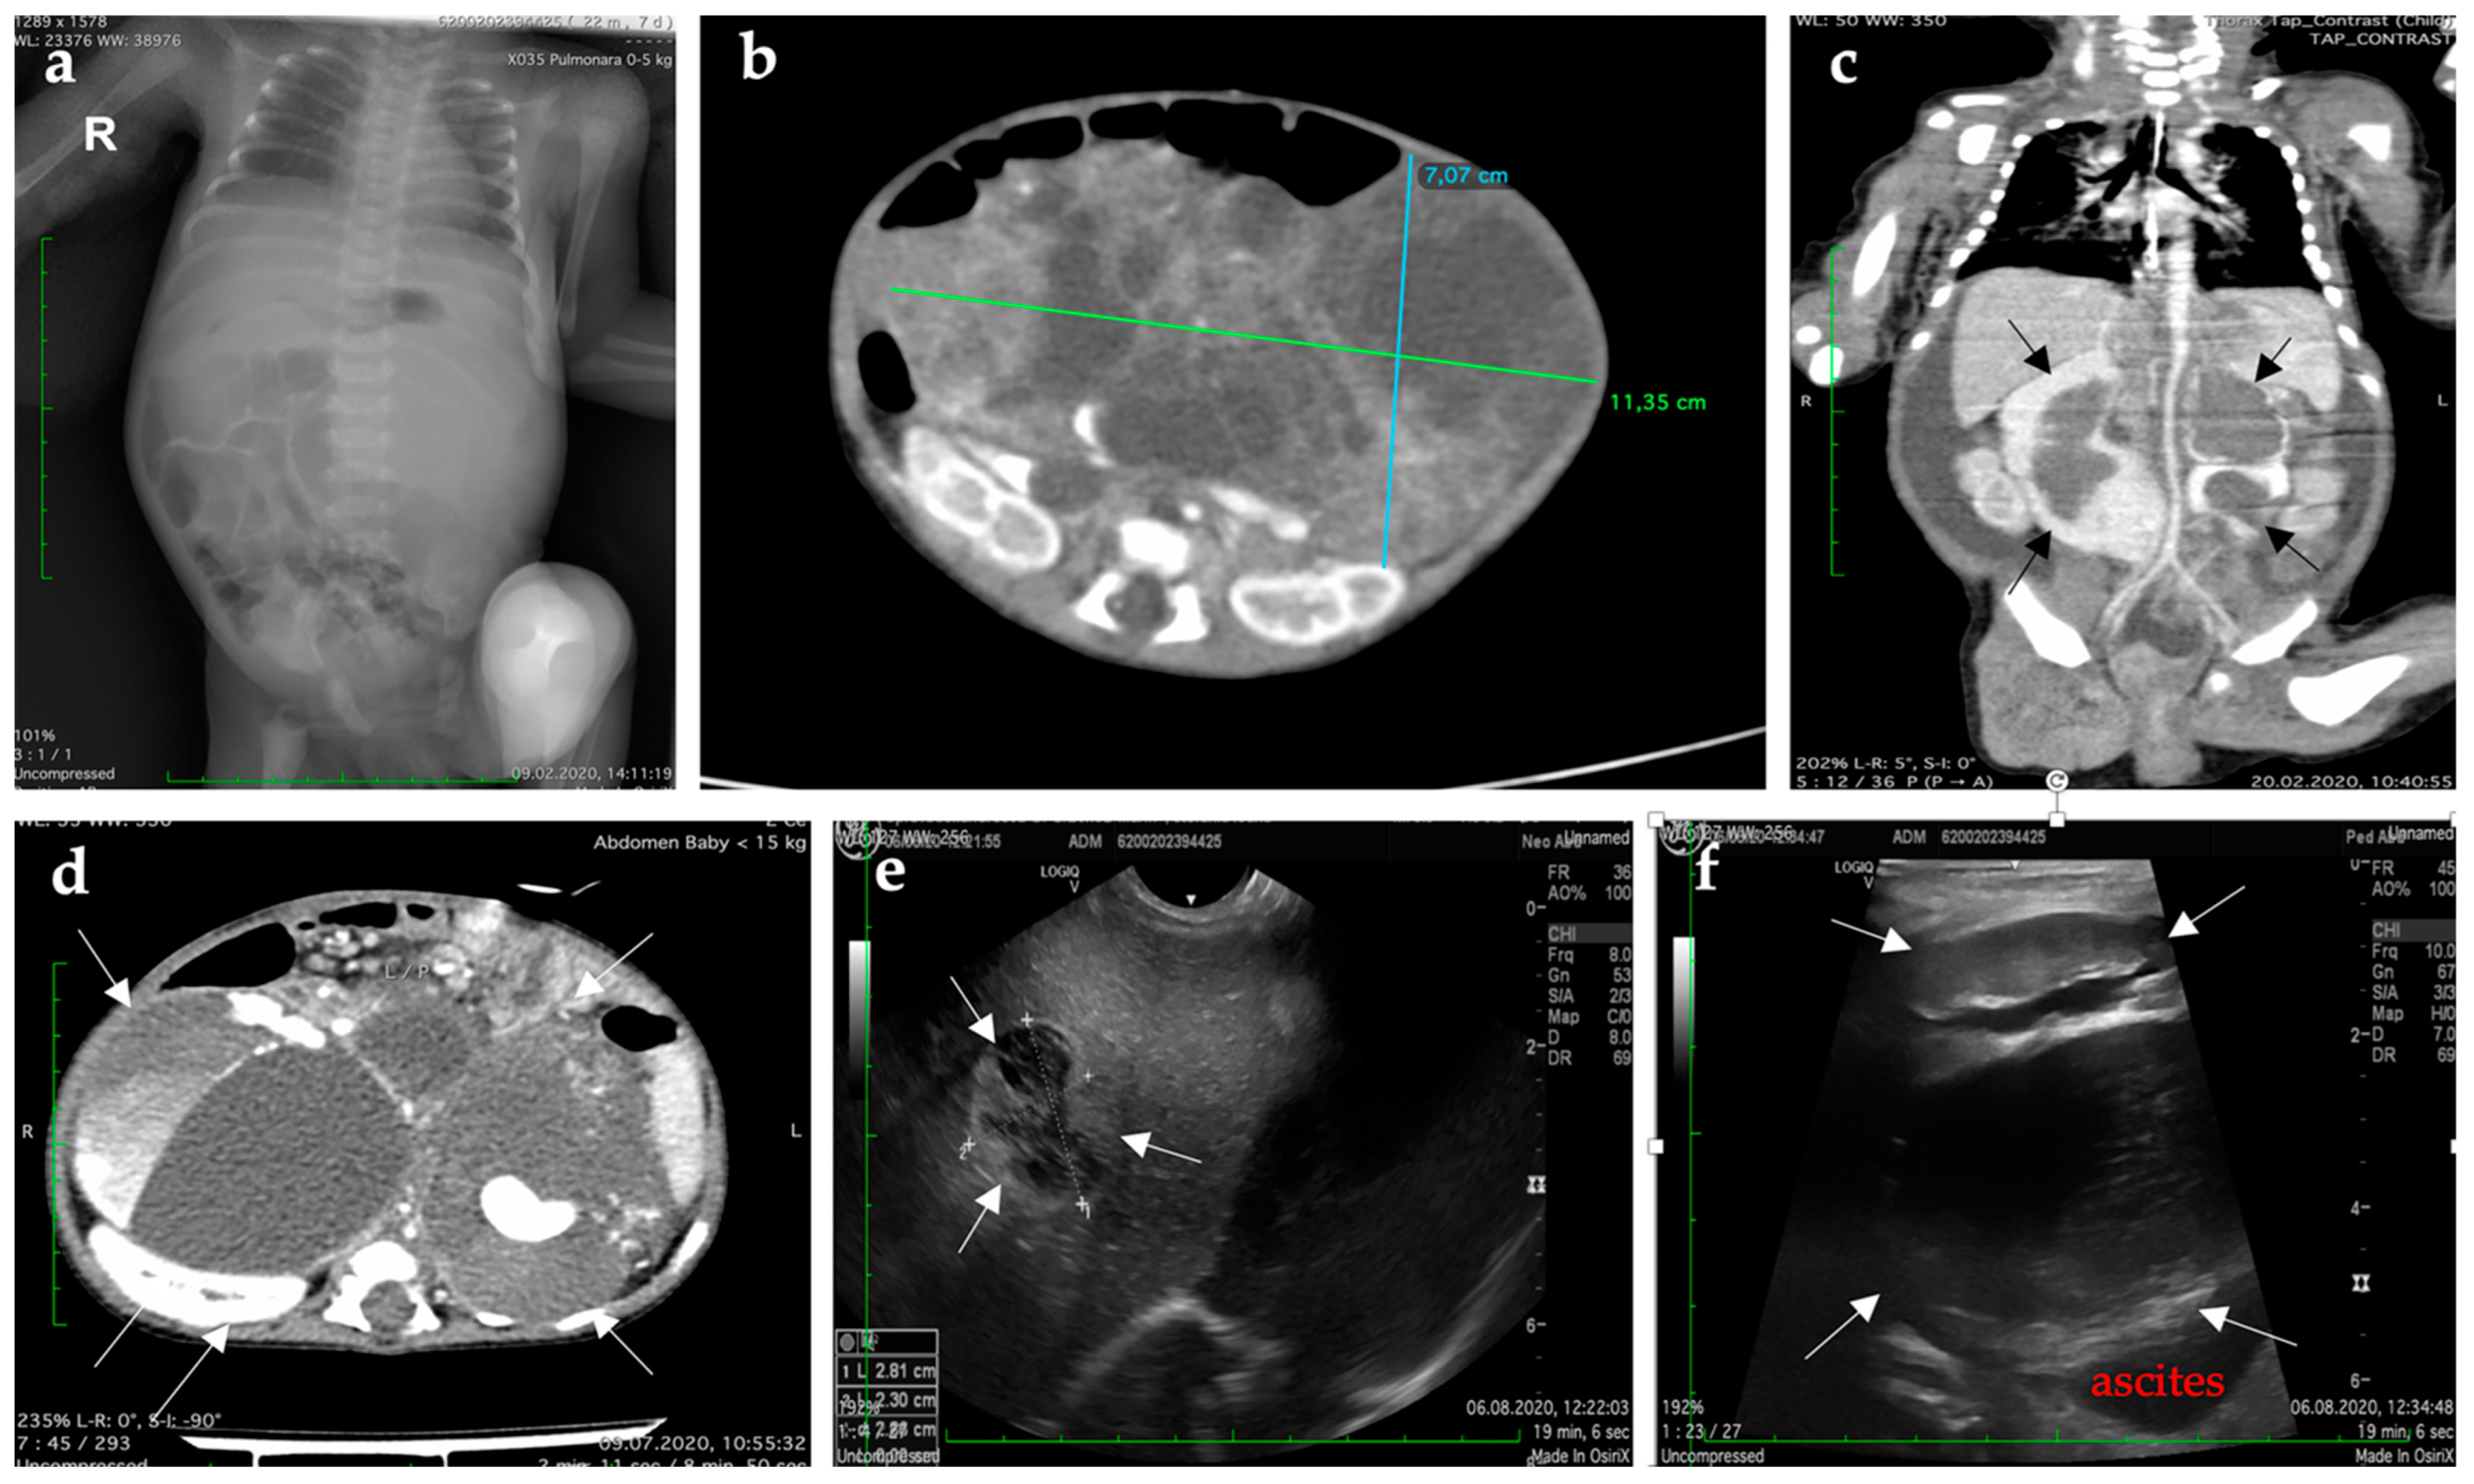

| Preoperative | Lung radiograph | 2nd day |

| CT of the thorax, abdomen, and pelvis | 6th day |

| Postoperative | CT of abdomen and pelvis | Three weeks |

| CT of the brain, thorax, abdomen, and pelvis | Four weeks |

| Abdominal ultrasound | Five weeks |

| Abdominal ultrasound | Seven weeks |